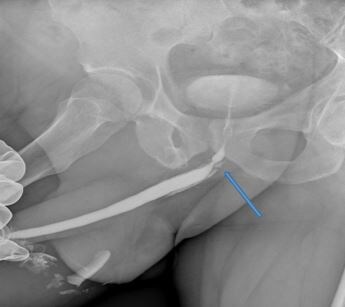

Когда мы регистрируем подобный график, проведя очень простое исследование – урофлоуметрию, мы для выяснения локализации и протяженности стриктуры уретры и определения степени сужения мочеиспускательного канала выполняем рентгеновское исследование – уретрографию. Вот так выглядела картинка уретрографии до операции (рисунок 2).

Рис. 2. Уретрография пациента до операции. Стриктура уретры показана стрелкой.

Это исследование представляет собой рентгеновский снимок мочеиспускательного канала, в который вводят жидкий рентгеновский контраст. Мы видим значительное рубцовое сужение мочеиспускательного канала, которое, судя по рассказу пациента, было связано с перенесенной несколько лет назад мочеполовой инфекцией. Пациента несколько раз лечили от мнимого «простатита», а диагноз стриктуры уретры был установлен нами впервые. Какого-либо дополнительного обследования пациенту не требовалось, ему сразу было предложено оперативное лечение (реконструктивная хирургическая операция) в объеме анастомотической пластики уретры.